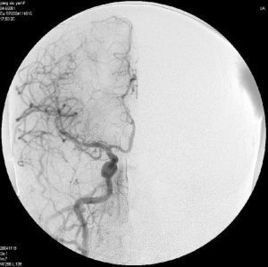

亦稱介入性血管造影學(Interventional angiography),是指在診斷性血管造影的同時,自導管向血管管腔內注射藥物或某些物質或施行某種措施,以達治療目的。常用血管介入技術有三種。

2、經導管血管栓塞法(Transcatheter embolization)

經原血管造影的導管或特製的導管,將栓塞物送至靶血管內,一是治療內出血如外傷性臟器出血、潰瘍病、腫瘤或原因未明的臟器出血。另一是用栓塞法治療腫瘤,因腫瘤循環部分或全部被栓塞物阻斷,以達控制腫瘤之生長,或作為手術切除的一種治療手段;亦可用於非手術臟器切除,例如注射栓塞物質於脾動脈分支內,即部分性脾栓塞,以治療脾功亢進,同時不影響脾臟的免疫功能。